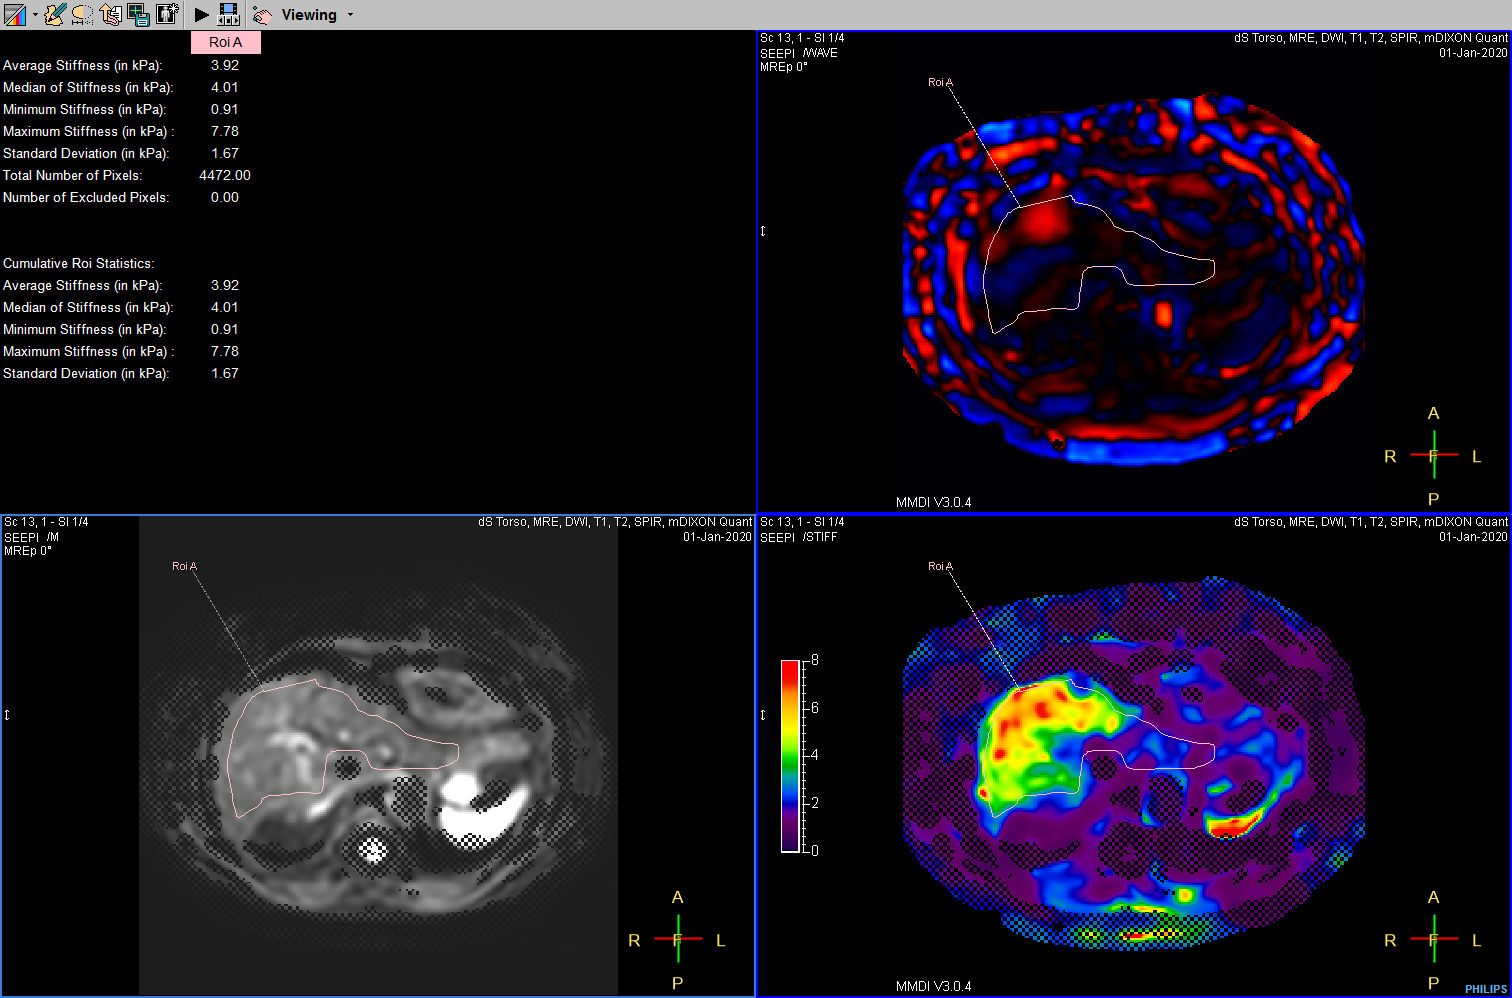

Liver ExamCard including single breath hold 3D mDIXON Quant for non-invasive liver fat quantification of the whole liver with high accuracy (± 3.5%) and reproducibility (± 1.4%)1. And MR Elastography for a non-invasive assessment of differences in tissue stiffness of the liver. Image processing is fully integrated at the scanner with automated calculation of Elastograms, reflecting tissue stiffness in kPa and statistical confidence map for reliability assessment.

MR Elastography (SE-EPI, 4 slices) (Stiffness Map)

MR Elastography (SE-EPI, 4 slices) (processing)